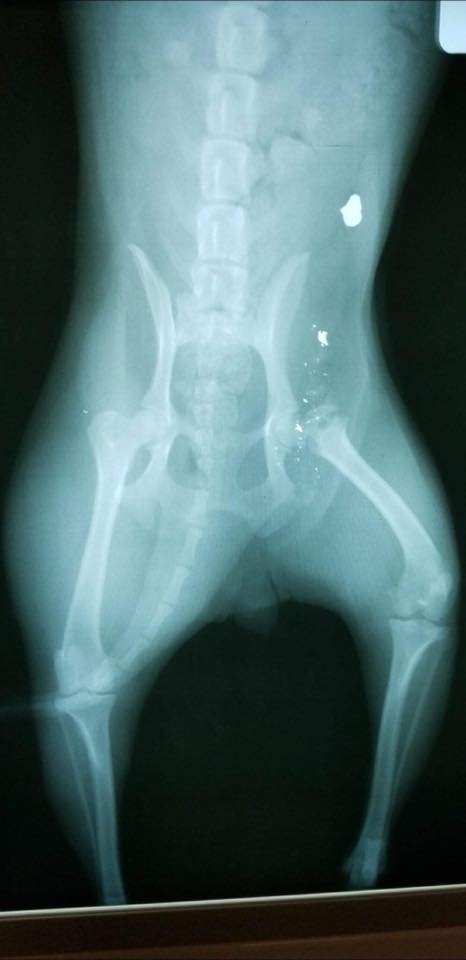

She arrived at a shelter Saturday with bullet wounds that shattered her hip. Surgery will be necessary to replace her hip and remove the bullet shards.

We have an update on the poor girl that came into a West Virginia shelter with the bullet wound and shattered hip. Her name is Buffy. It seems her femoral bone may be too shattered for a hip replacement. Unfortunately her leg and part of the hip will need to be amputated. It isn’t the news we were hoping to hear but are still grateful her life will be saved. We have witnessed firsthand that dogs have an amazing ability to adjust to life on three legs. We have faith that Buffy will do the same! Keep her in your prayersÂ

Hello everyone! Here I am in my first post recovery picture! The surgery went well to remove the bullets and my shattered hip. I am in very good spirits and am being well cared for in a foster home while final arrangements are made for my transport to Action for Animals. Thank you to all my new friends at Lauren’s Wing who helped make my surgery possible! xoxo Buffy